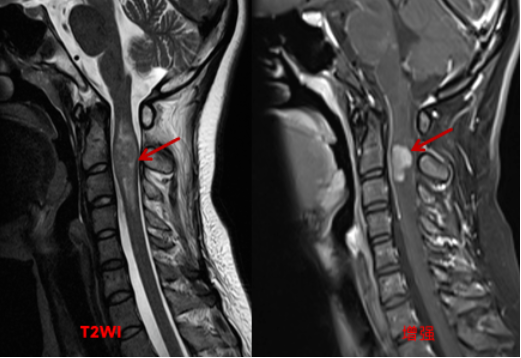

颈椎MRI平扫+增强扫描检查,提示颈2-3椎体水平脊髓增粗,相应节段脊髓中央区可见椭圆形稍短T1稍长T2信号,边界尚清,增强扫描病变内可见明显不规则结节状强化,强化结节大小约15x25mm。